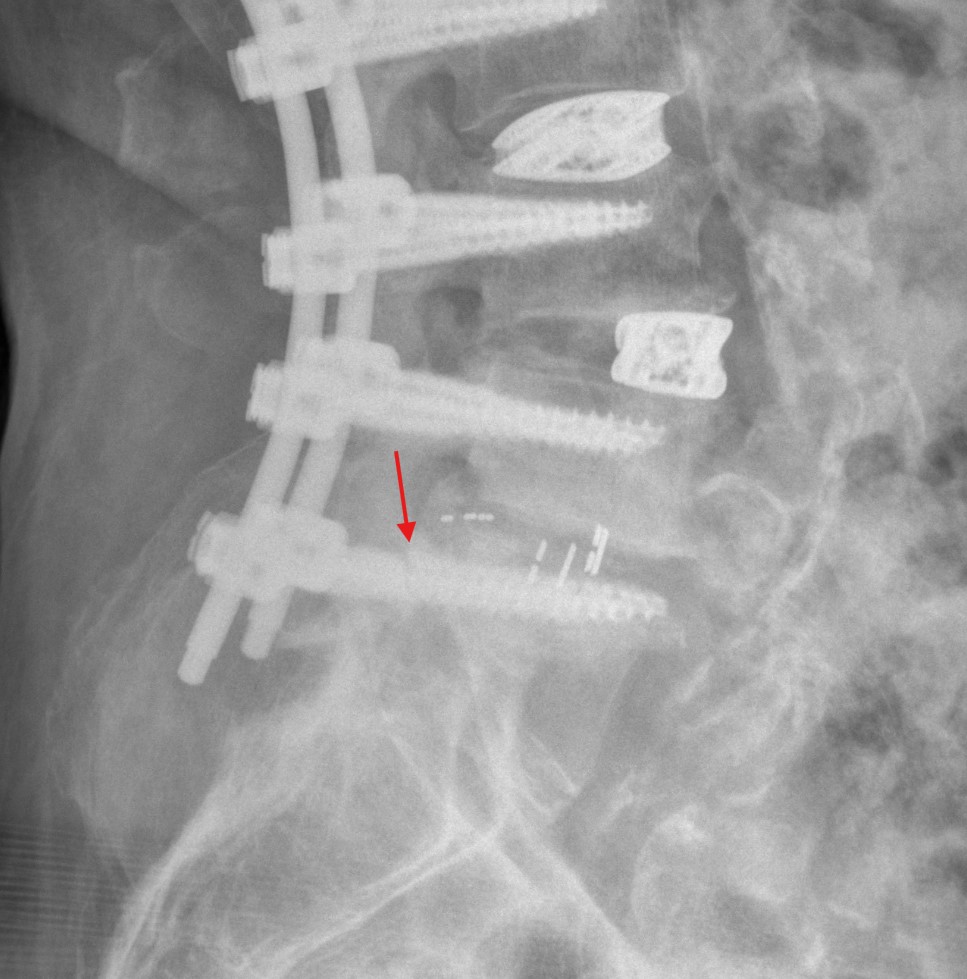

Herkömmliche Pedikelschrauben verursachen in der MRT Bildgebung Artefakte, sodass die MRT Bildgebung als suboptimal zur Beurteilung von Pedikelschrauben gilt. Der Goldstandard zur Lagebeurteilung von Pedikelschrauben ist die CT-Bildgebung.

Pedikelschraubenfehllage

Pedikelschraubenmigration

Als Pedikelschraubenmigration bezeichnet man das "wandern" der Pedikelschraube von der ursprünglichen Position.